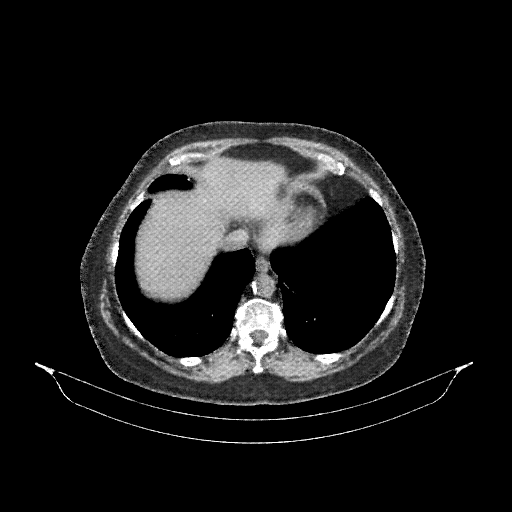

Reconstructed NATIVE CT scan (cycle consistency)

No window - Raw intensity values

Lung window (WL -600, WW 1500 β†’ Low βˆ’1350, High +150)

Mediastinum window (WL 40, WW 400 β†’ Low βˆ’160, High +240)